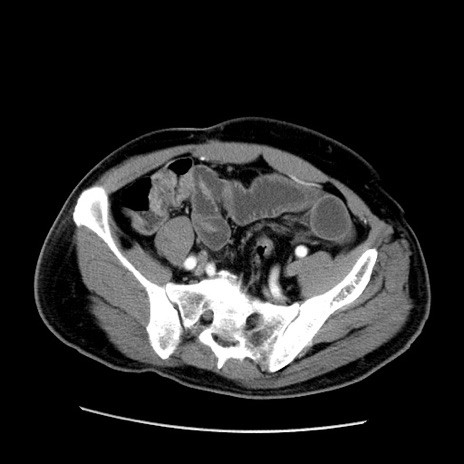

症例22(横断像)

【症例】50歳代男性

【主訴】腹痛

【現病歴】AVMからの被殻出血のため回復期リハ病棟入院中。 本日午後3時頃急に下腹部痛が出現した。

【既往歴】AVM、被殻出血、虫垂炎、高血圧

【身体所見】意識晴明、左半身不全麻痺、会話の理解は良好、36.5°C、腹部:膨隆、全体に板状硬、下腹部正中に圧痛点あり、反跳痛-、筋性防御不明、右下腹部にope scar

【データ】WBC 9400、CRP 0.06